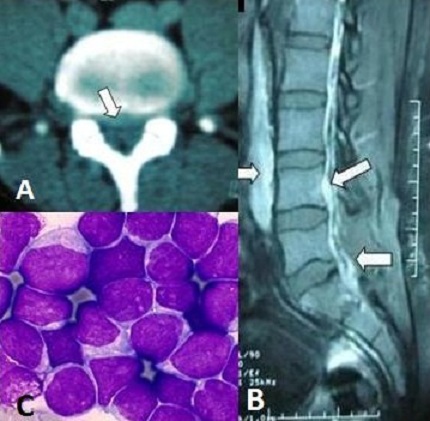

This 32-year-old-man was admitted to the emergency department because of S1 left acute sciatica. An emergency, CT-scan showed highly probable appearance of herniated disc in L5-S1 level (A). The patient was operated without founding disc herniation, but an aspect of anterior and posterior epidural abscess compressing the dural sheath at L5-S1. Medullary MRI showed after the up and the down extention of disease process (B). Histological examination of samples found a B lymphoblastic leukemia (C). The patient died 3 weeks after because of systemic infection. After review of literature, it was never been described that the sciatic pain can be a mode of revelation of B acute lymphoblastic leukemia. Only two cases reported this mode of revelation but for lymphoma requiring a surgical intervention -as our case- firstly to relieve the patient by a radicular decompression and secondly for histological diagnosis.